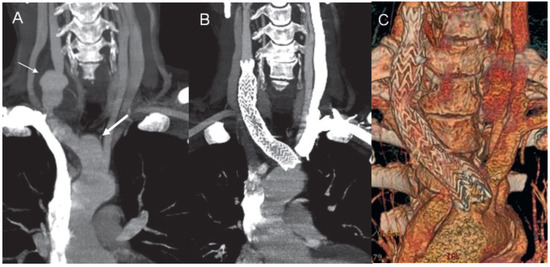

An Unusual Case of Large Vessel Vasculitis Associated with Pyoderma Gangrenosum: The Natural History of the Disease

by Julija Klimusina, Michel Oberson, Marcello Di Valentino, Michel Ruchat, Rolf Wyttenbach, Mario Alerci, Jeanne Marie Segatto, Andrea Menafoglio, Claudio Marone, Ludwig K. von Segesser and Augusto Gallino

Cardiovasc. Med. 2011, 14(6), 185; https://doi.org/10.4414/cvm.2011.01595 - 29 Jun 2011

We report a case of a patient with a long history of pyoderma gangrenosum (PG), in whom large vessel vasculitis, most likely Takayasu arteritis (TA), manifested many years after the diagnosis of PG and showed a rapid progression within four years, resulting in [...] Read more.

We report a case of a patient with a long history of pyoderma gangrenosum (PG), in whom large vessel vasculitis, most likely Takayasu arteritis (TA), manifested many years after the diagnosis of PG and showed a rapid progression within four years, resulting in two invasive interventions. We describe the challenges of the management of the disease in our patient, the application of new pharmacological agents and the natural history of this rare disorder. Full article